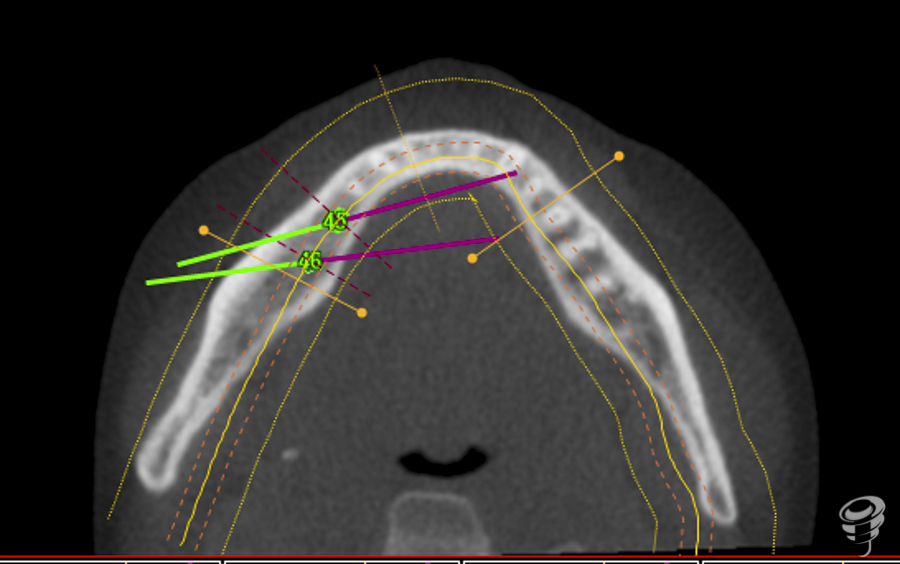

La cirugía guiada permite la planificación de implantes virtuales en el conjunto de datos aportados por la exploraciones tridimensionales del Tac, permitiendo una predeterminación exacta del tratamiento y la transferencia de la planificación de la rehabilitación al campo operatorio.

A.M.R Paciente de 40 años de edad, de sexo femenino, edéntula parcial, no fumadora y sin antecedentes médicos de interés. La paciente fue evaluada radiológicamente con una tomografía computarizada de haz cónico y se procedió a la planificación de su caso mediante el sistema informático Galimplant 3D Exacto®. Se planificaron dos implantes galimplant de 4X10mm (IPX 4010).

Una vez realizada la planificación de los dos implantes, se lleva a cabo la impresión de la férula quirúrgica dento-soportada con dos orificios cilíndricos adaptados a la fresa pin de 2 milímetros de diámetro. Esta fresa tiene la función de guiar tridimensionalmente la posición del implante.